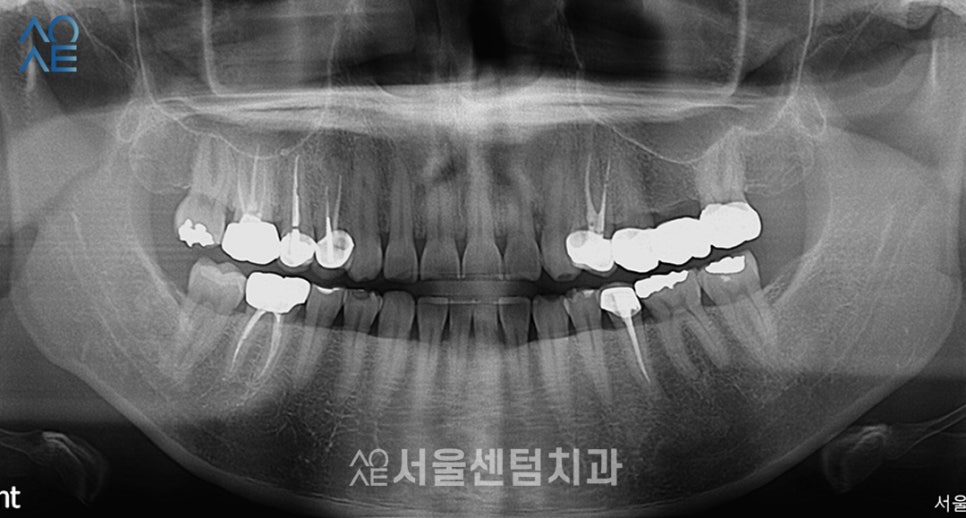

모든 치과 치료를 시행하기에 앞서

전체 구강 환경을 면밀하게 파악해야 합니다.

해당 부위에 충치가가 없는지

치주 질환이 심하지 않은지 등

여러 측면에서 분석해야 하기에

구강 검사를 실시하고 있습니다.

위 환자분께서는

이전에 레진치료, 신경치료를 받으셨지만

현재는 충치가 없다는 점이

파노라마 사진을 통해 파악이 되었습니다.

다행히 충치치료는 할 필요가 없으니

이갈이와 라미네이트 치료에 대해서만

집중하기로 했습니다.